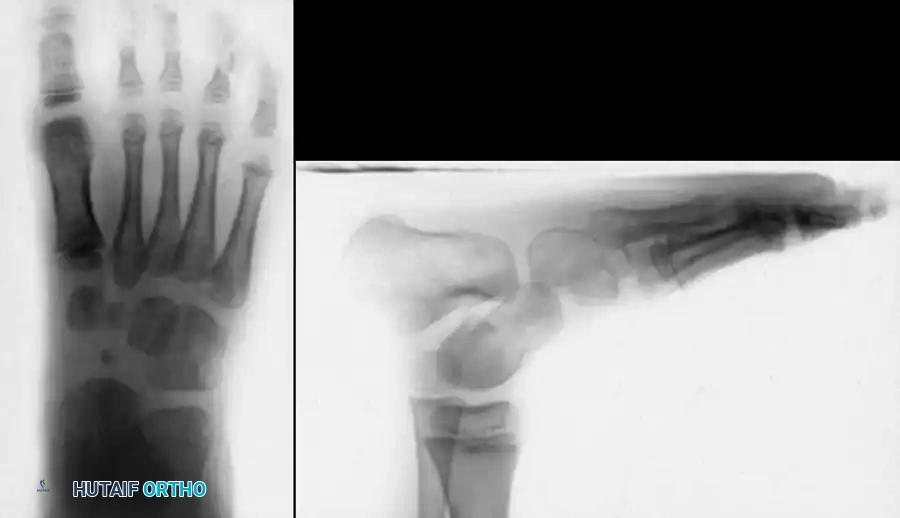

RADIOGRAPHIC EVALUATION

Radiographs are an indispensable adjunct before, during, and after treatment to ensure that clinical correction correlates with true osseous realignment. In the non-ambulatory child, standard imaging includes anteroposterior (AP) and stress dorsiflexion lateral radiographs.

• AP Talocalcaneal Angle (Kite's Angle): Normal is 30 to 55 degrees. In clubfoot, the talus and calcaneus are nearly parallel, progressively decreasing this angle toward 0 degrees as heel varus worsens.

• Lateral Talocalcaneal Angle: Normal is 25 to 50 degrees. In clubfoot, this angle decreases significantly.

• Stress Lateral Tibiocalcaneal Angle: Normal is 10 to 40 degrees. In clubfoot, this angle is often negative, indicating severe calcaneal equinus relative to the tibia.

• Talus–First Metatarsal Angle (AP View): Normal is 5 to 15 degrees. In clubfoot, it is usually negative, reflecting severe forefoot adduction.

Image

Fig. 7: Radiographic evaluation. (A) AP view of a right clubfoot showing a decreased talocalcaneal angle and negative talus-first metatarsal angle. (B) Normal AP view. (C) Dorsiflexion lateral view of a clubfoot showing parallel talus and calcaneus (0 degrees). (D) Normal lateral view.